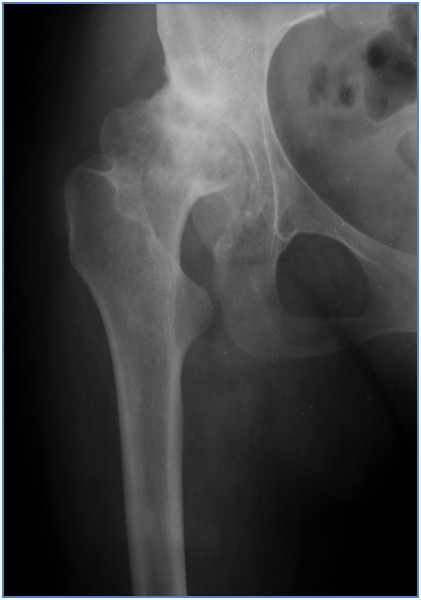

Na jaki typ zmian zwyrodnieniowych wskazuje przedstawiony poniżej radiogram stawu biodrowego?

Pytanie 63